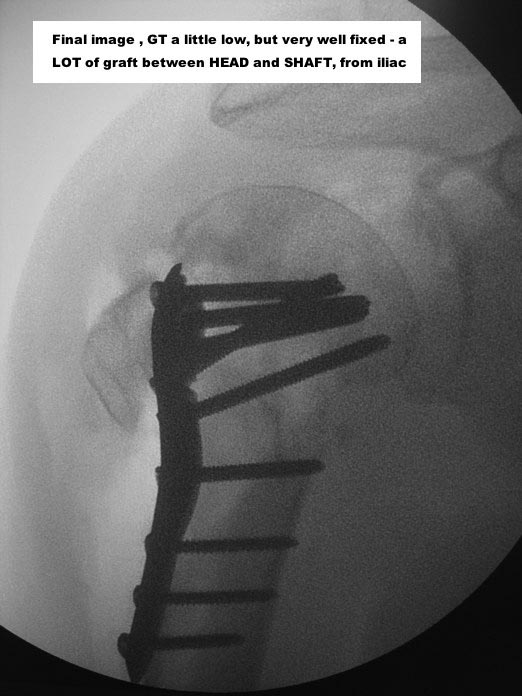

I would, for sure, use a tricortical iliac graft, between diaphysis and head

With a good PHILOS, surgeon must re-establish the best cephalic-diaphyseal angle (head-shaft relation) he can, and fix that

GT and LT shall be fixed with bony sutures, in usual fashion

Here are some photos, of chronic, locked, 4 part posterior dislocation, 2 months old, that I did September/2011. Patient is 67, very, very active - had a really reasonable, honest clinical result ...